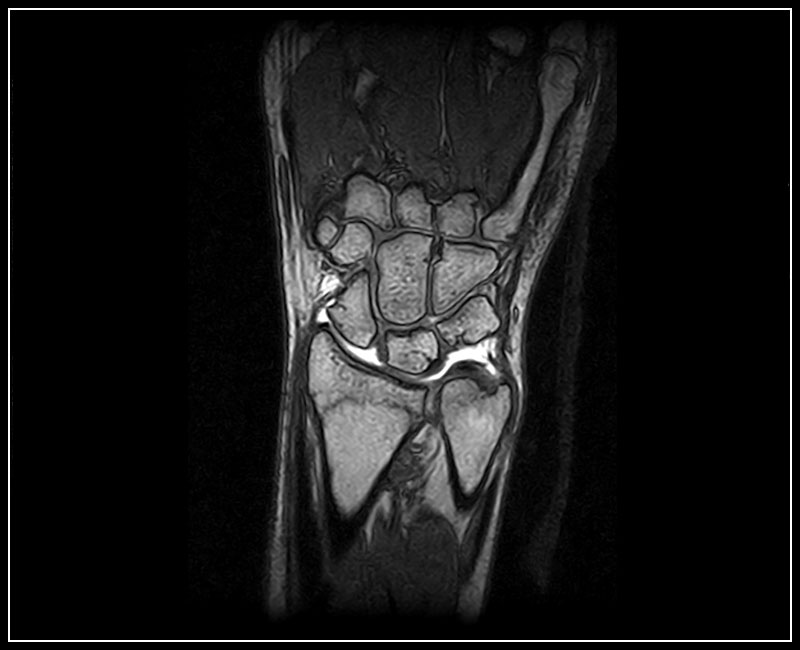

G-scan Brio obsahuje kompletní sadu  cívek speciálně navržených pro zobrazování MSK, což zaručuje velmi vysokou citlivost a pohodlí pacienta.

• Velký výběr specializovaných cívek MSK, celkem 10 různých cívek zaměřených na všechny anatomické oblasti

Klinické snímky